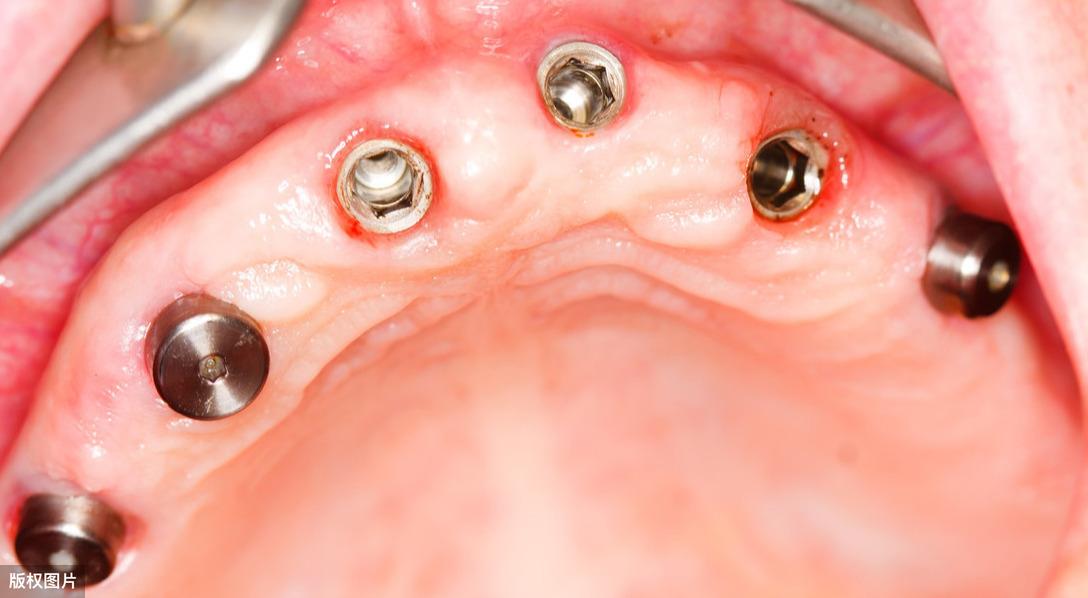

● 種植手術(shù)一期:常規(guī)局部麻醉下,使用專用的種植機器將人工牙根(種植體),植入到缺牙區(qū)的牙槽骨內(nèi)。整個手術(shù)操作的時間約為30分鐘左右,術(shù)中不會有疼痛感,術(shù)后因每個患者的情況不一樣可能會有腫痛的癥狀,對應(yīng)的可以預(yù)防使用抗生素防止感染。

● 種植手術(shù)二期:一期人工牙根(種植體)植入后,需等待4-6個月待種植體與牙槽骨形成“骨結(jié)合”后,開始安裝一個特殊的部件-愈合基臺,它能夠使種植牙穿出牙齦。接下來繼續(xù)等待約1個月左右,待牙齦軟組織成型后,就可以開始制作牙冠了。